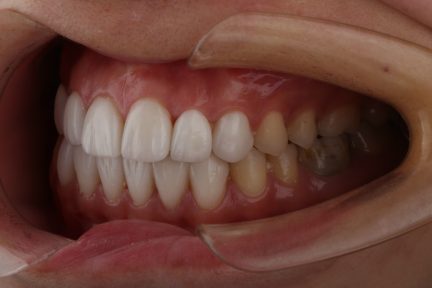

État final

- Relation de Classe I obtenue

- Guidage fonctionnel des canines des deux côtés

- Surplomb et recouvrement normaux obtenus

- Après traitement orthodontique, la partie supérieure droite 3, un implant posé et toutes les dents antérieures ayant reçu une restauration esthétique ont été utilisées.